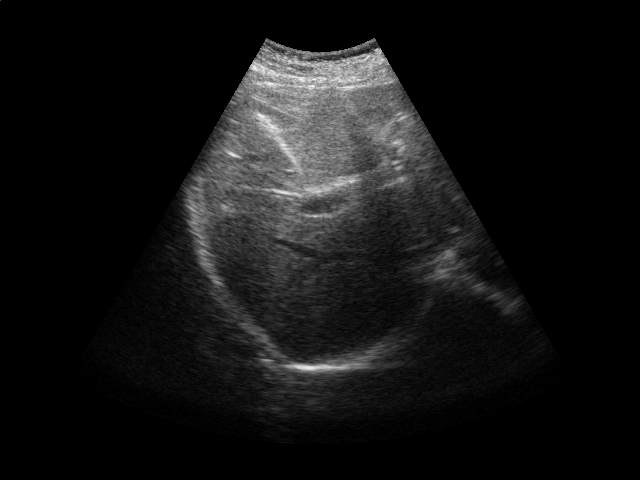

Refer to caption

Figure 2: Ultrasound gating. Top: Ultrasound images of the liver over time (abdomen, right upper quadrant). Bottom left: Correlation coefficient vs. error tolerance ε𝜀\varepsilon. Bottom right: The number of support vectors vs. error tolerance ε𝜀\varepsilon. Both figures in the bottom report results for different values of kernel ridge regression regularization parameter λ𝜆\lambda.

Respiratory gating tracks a patient’s breathing cycle, which has numerous applications such as 4D imaging, radiation therapy, and image mosaicing [16]. Manifold learning has been used for highly accurate respiratory gating of ultrasound images [23], where 4D data reconstruction was achieved with retrospective gating, i.e., the gating was calculated after the data acquisition was finished. We extend this work to attain real-time gating. A small number of breathing cycles are acquired and used as input for manifold learning to construct the respiratory signal, as is done for retrospective gating. The new incoming stream of ultrasound images is then gated by performing an out-of-sample extension.

We conduct experiments on five 2D ultrasound image sequences of the human liver acquired during free breathing; example images are shown in Fig. 2. Each sequence contains 640×\times480-pixel images and vary in length between 298 and 371 frames captured at 33 Hz. For a given image sequence, we use each image in the sequence as an input data point for learning a 1D manifold with Laplacian eigenmaps [4]; we use a 9-nearest-neighbor graph with an associated heat kernel of temperature t=10𝑡10t=10. The 1D embedding learned using an entire sequence of images serves as a reference signal for evaluating our sparse out-of-sample extension versus kernel ridge regression as the baseline. In what follows, we compare the 1D embedding of our sparse out-of-sample extension to the reference signal by computing a correlation coefficient between them. We use kernel ridge regression as a baseline method. Here we train on the first 200 frames and test on the remaining frames. We then compare the results with those obtained by training on all frames, as would be done for retrospective gating.